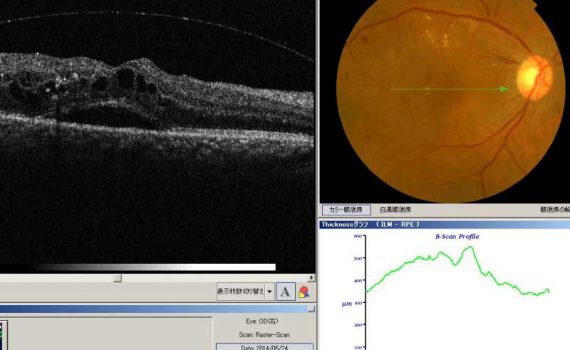

中心性漿液性網脈絡膜症

中心性漿液性網脈絡膜症は,略して中心 […]